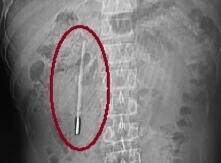

水银体温计“潜伏”肚内20年 随时可能引发肠穿孔大出血